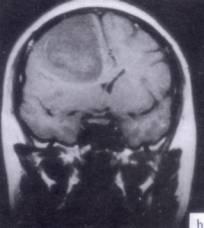

病历摘要:??患者男性,52岁。头痛伴呕吐2月,呕吐呈喷射性。既往身体健康。体检:神清,表情淡漠,反应迟钝,双眼底视神经乳头明显水肿,左鼻唇沟稍浅,左腹壁...

问题 病历摘要:??患者男性,52岁。头痛伴呕吐2月,呕吐呈喷射性。既往身体健康。体检:神清,表情淡漠,反应迟钝,双眼底视神经乳头明显水肿,左鼻唇沟稍浅,左腹壁反射减弱,左上下肢肌力4级,左Babinski征(-)。 下列的术后处理哪些是正确的?